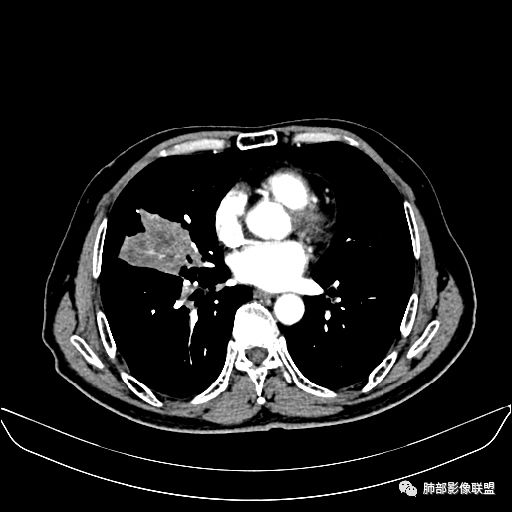

住院4天后行胸部增强CT

动脉期

老年男性,因“咳嗽咳痰1月余。”入院。病程中咳嗽咳痰,咳黄白痰,间断咯少许鲜红色痰血。PPD阳性。胸CT:右肺中叶外侧段支气管管腔阻塞,大片实性病变,病灶边缘光滑,部分边缘膨隆,可见分叶,肺门及纵隔可见肿大淋巴结,并可见钙化。增强可见病灶明显强化,而且延迟强化明显,病灶内多发低密度区,内见血管影,血管变细、部分血管破坏。考虑恶性病变可能性大,鉴别慢性肉芽肿性病变。

胸CT:跨叶大肿块,主体在中叶,右中叶外侧段支气管阻塞,病灶部分边缘膨隆,可见分叶,部分边缘平直,肺门及纵隔可见肿大淋巴结。增强病灶不均匀强化,延迟强化明显,病灶内多发低密度区,内见血管飘浮,部分血管变细、模糊。考虑:恶性病变可能性大,大细胞?淋巴瘤?鉴别慢性肉芽肿性病变。

右肺中叶软组织肿块,外围向内生长,叶间胸膜向前内移位,肿块近肺门侧跨叶,中叶外侧段支气管截断,密度不均匀,双侧肺门及隆突下见肿大淋巴结,增强后呈中度不均质强化,肺动脉供血,多发坏死区,边界尚清,坏死区域内见结构,结合病史考虑恶性,鉴别诊断1结核,爬行征是沿支气管树分布,外宽,内窄,周围有卫星灶,内气管狭窄后扩张,此例沿叶间胸膜长轴分布,气管有截断,不典型。2炎性肉芽肿,符合的地方下方层面增强后延迟性轻度环形强化,不符临床无发热等急性感染病史,实验室指标不符,病灶周围渗出及慢性炎性改变有,不明显。

吴婧老师和南边老师都对该病例进行了深入分析。从支气管管壁的增厚,支气管狭窄后扩张,支气管粘液栓,病灶形态,到病灶不均匀强化及坏死彻底,到周边病灶及肺组织空气的潴留,加之纵隔内淋巴结肿大伴钙化等等,都支持慢性炎性病灶,尤其是结核。

墨西哥仙人掌征---结核        影像上结核灶,粗大的均匀枝干,推测是支气管囊状扩张引起的,在非支气管区,形成圆形坏死囊群;如果这些坏死比较稀薄,又遇到扩张支气管,就会形成粗大的“墨西哥仙人掌”。结核引起的支气管近端炎症纤维化,可以造成支气管阻塞,从而将干酪样坏死物封堵在管腔内。仙人掌主干内部应该是干酪为主,稀薄的,具有流动性,时间久了会出现钙化。

结核坏死与鳞癌鉴别有一点是结核坏死没有方向性,鳞癌有。鳞癌靠近支气管近端部分,血供容易维持,不易坏死,所以坏死靠外侧。而结核干酪样坏死,把一定体积的流动性坏死物,包裹起来,什么形状最省料?坏死物包裹,表面积最省的自然是圆球形,而遇到支气管,坏死物一多,就把支气管撑大了。包裹物是就地取材,扩张的支气管就成了包裹结构。